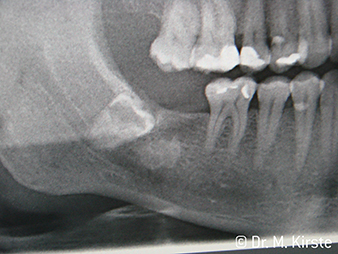

W&H Patient example

Fig. 7: ... is neatly removed using the new contra-angle handpiece.